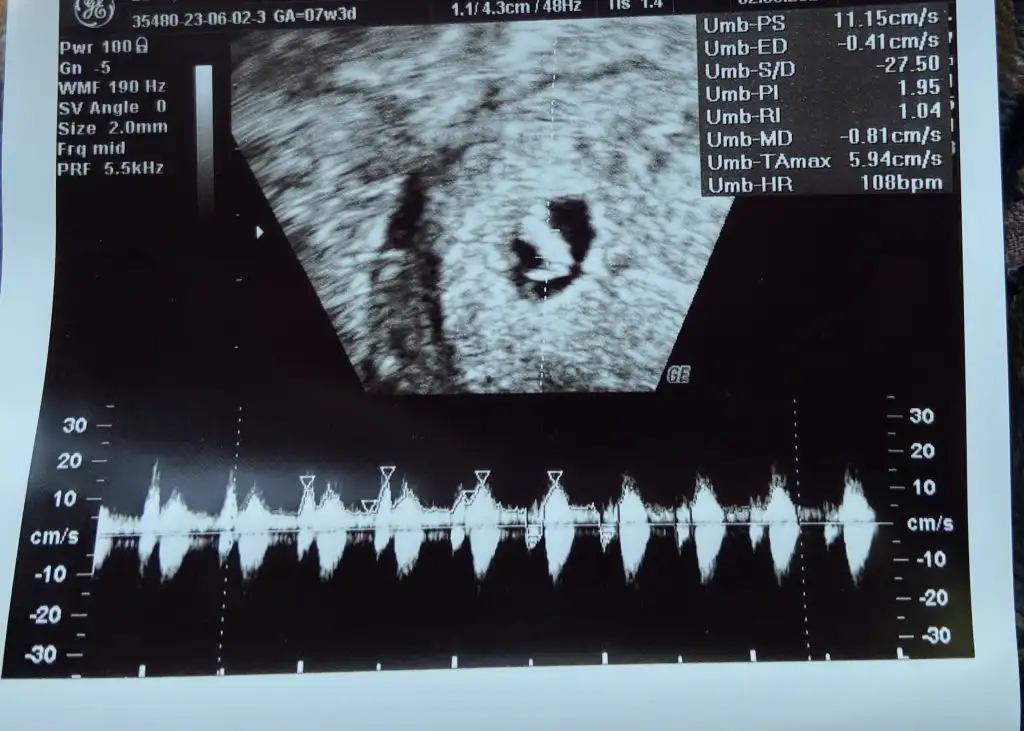

Bugun gittigimde doktor karindan ultrason ile bakti, bakti ve hicbir goruntu alamiyorum dedi ve transvajinal muayeneye gonderdi. Doktor ofisinde o tip makine yok maalesef. Neyse orada gordum, kalp atisini da duydum. Rahmim ters oldugu icin goruntu alirken canim acidi ve sabit goruntu almak mumkun olmadi yani olcumler yokAma doktor bebek 8-9 hafta arasinda bir yerde olmasi geren buyuklukte ve saglikli dedi. Kalp atisi da 179 diyor, heyecanli bir bebe galiba. Yani kalp atisi duyamayanlar uzulmeyin. her zaman olumsuz bir sey demek degil. Bugun vajinadan bakan doktor da inanin degisik hareketler ve pozisyonlardan sonra gorebildi bebegi. Ve neden kalp atisi icin bu kadar beklediklerini daha iyi anladim, bugune kadar boyle bir hissim yoktu ama kalp atisini duydugum an inanilmaz baglandim... Bir daha hamile kalsam 12. haftadan once duymak istemem belki,dusuk vs tehlikesi minimize olduktan sonra duymak isterim cunku kendi adima beni korkunc derecede etkiledi.